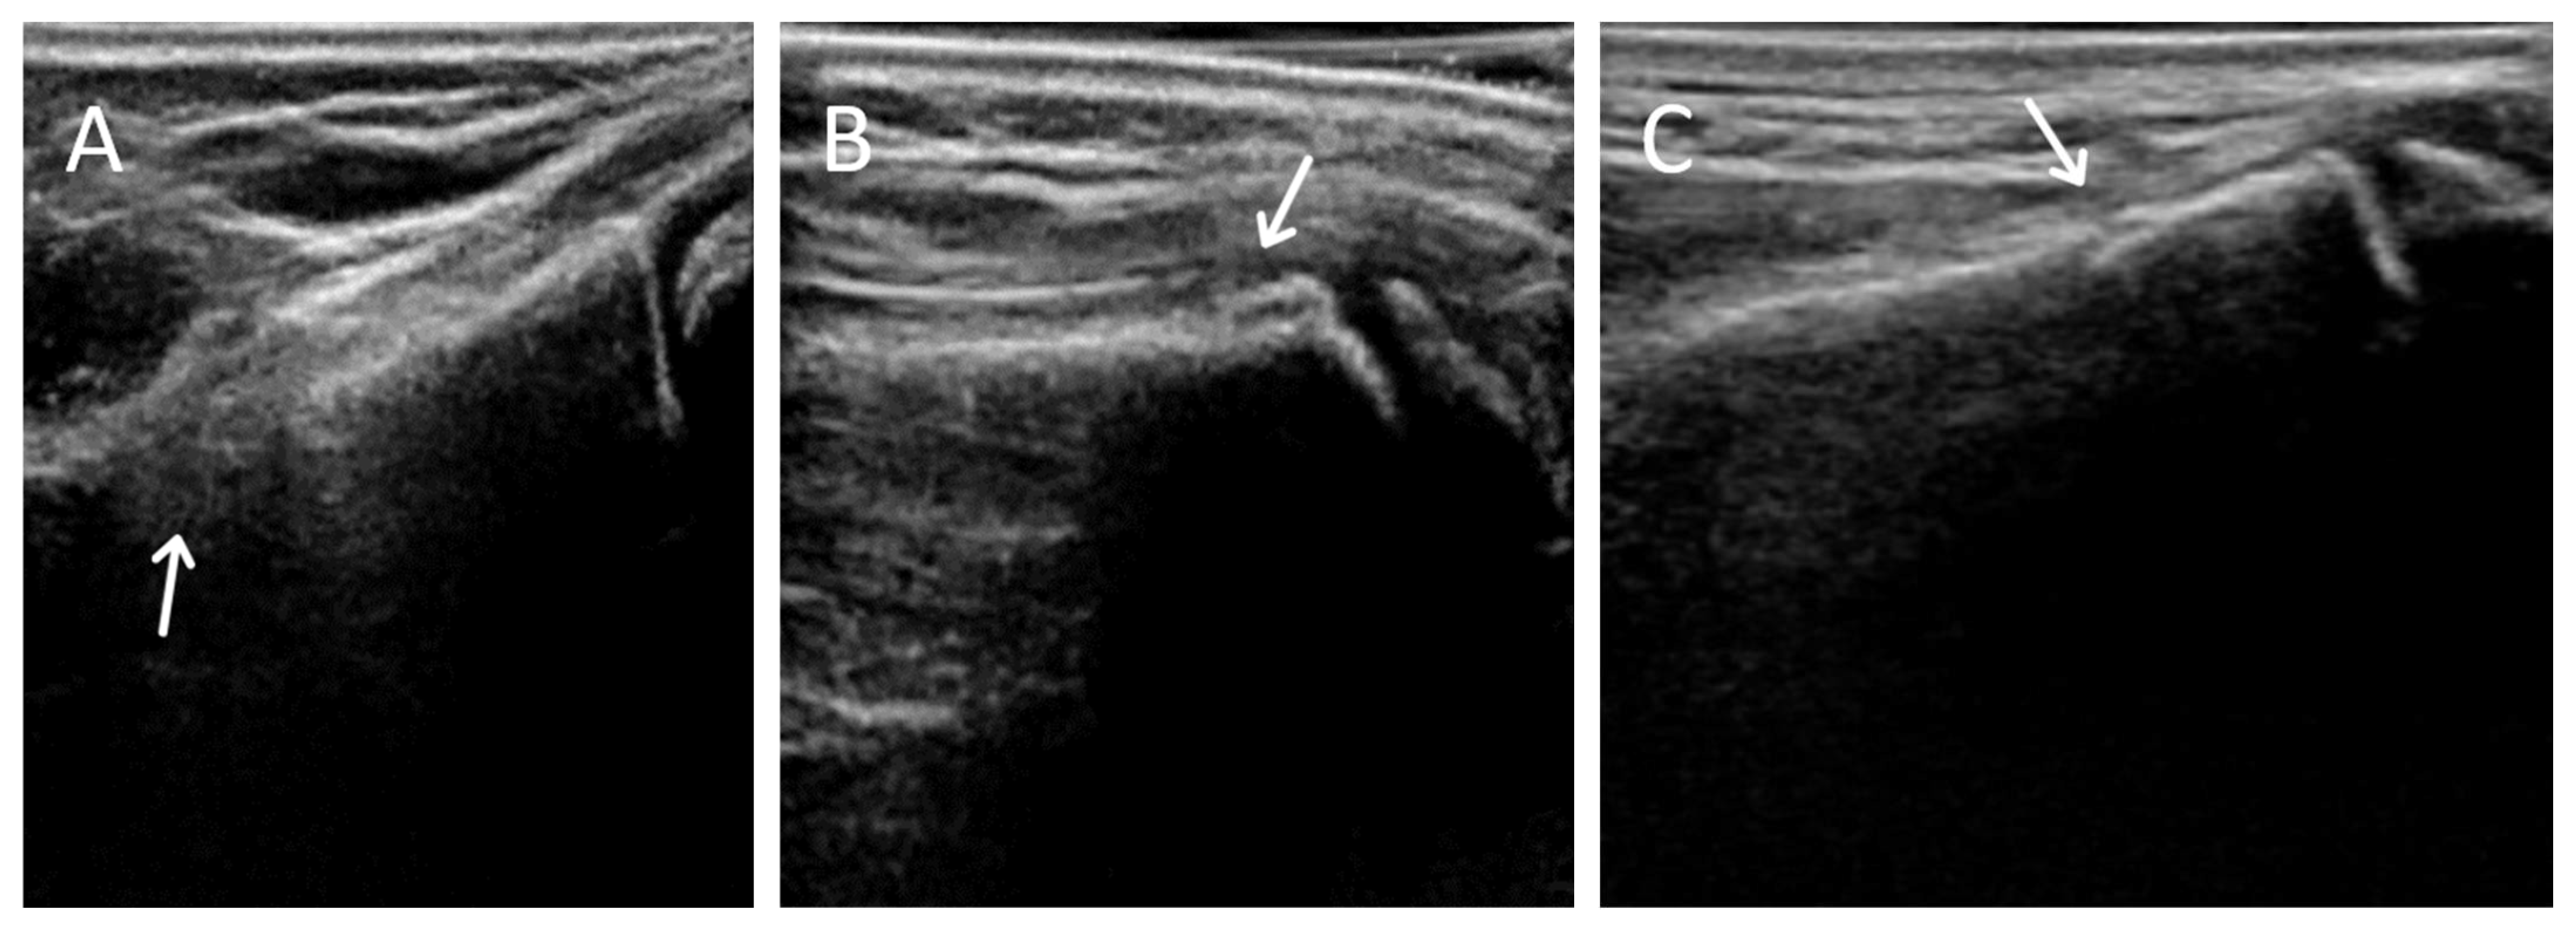

There were 2 possible radiographic false negatives out of 10 negative radiographs, as the US revealed subtle cortical irregularities that could represent undisplaced fractures. Retrospective review of two X-rays in light of ultrasound findings showed subtle cortical contour irregularities that might have represented the fractures identified on US (Figure 3). Previous studies had also reported the possibility that ultrasound may identify subtle fractures not seen on radiographs [7]. The clinical significance of these possible undisplaced fractures is unknown. Future study could potentially perform limited MRI in this small subset of patients with discrepant ultrasound/X-ray findings to clarify vs. an external gold standard.

Figure 1. Possible missed fractures. (A,B) are dorsal longitudinal views of the distal radius of two possible X-ray false negatives. Note the excess angulation of the distal radius may represent torus fractures. The possible defect is observable on X-ray.